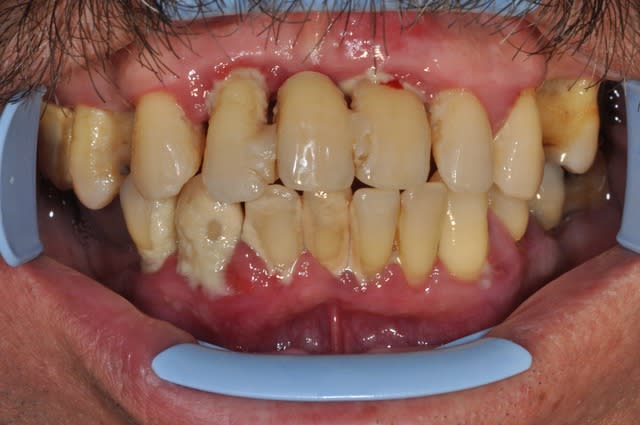

26 ans et toutes ses den... Ha non !J'ai les dents toutes pourrites (un classique)

CMU de mère en fille, je fais quoi je dégage tout ou je ceramise tout ce qui reste ... :)

Vous remarquerez le bel effort du confrère sur 21,22 et 23.